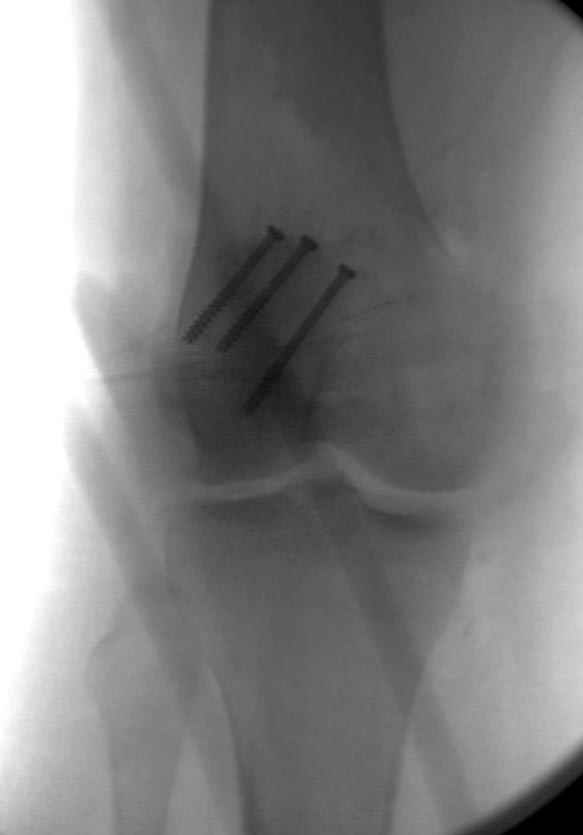

Сегодня досылаю остальные снимки, которые не прошли вчера. Как вчера писал, после фиксации перелома надколенника с дефектом кости и собственной связки, наложили ваккуум и наружный фиксатор. (снимки 4-9)

Внешний фиксатор держим около 6 недель, поэтому был выбран метод фиксации шурупами и еще линия перелома была диагональной, не было нужды в tension band technique, cannulated screws удобнее, провел спицы и по ним шурупы.